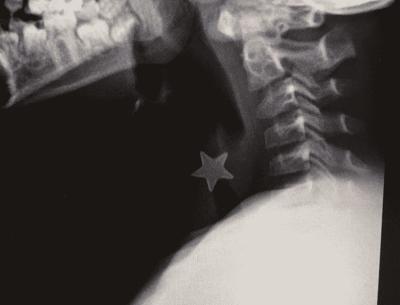

Aveva una stellina di metallo del diametro di 1 centimetro e mezzo, ferma nella trachea e inalata da più di 24 ore, un bambino di 8 anni che rischiava per questo di soffocare e che è stato salvato grazie a un intervento d’urgenza all’ospedale Niguarda di Milano, dove era stato inviato nella notte con un trasporto d’urgenza da un altro ospedale milanese.

“Abbiamo deciso di intervenire nell’immediato. Il piccolo infatti era gravemente asfittico nonostante la stellina fosse stata inalata da tempo, da circa un giorno – spiega Massimo Torre, direttore della Chirurgia toracica – Non si poteva aspettare oltre, alle 2 della notte la sala operatoria e l’équipe erano pronti per la procedura di rimozione”.